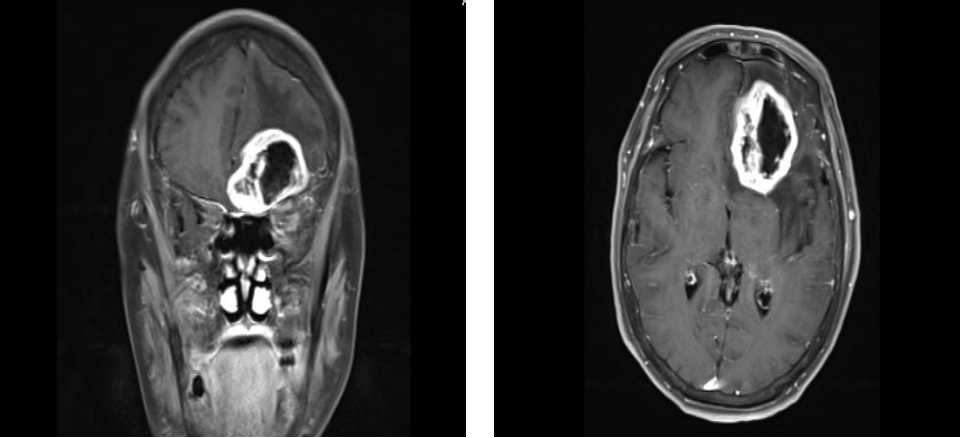

左起:图4a图4b

图4a同一患者的左侧额叶颅内占位(冠状位)

图4b同一患者的左侧额叶颅内占位(横断位)